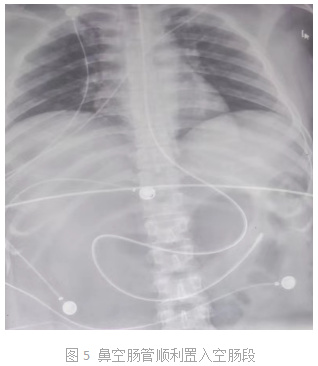

鼻空肠管置管的x线判定

腹部x线是判断鼻肠管末端位置的金标准

可以通过听诊,测定消化液的ph,以及拍摄腹部x线片来进行位置的判断.

食管,胃部,幽门,十二指肠置入到空肠位置,经术后x线检查证实鼻肠管